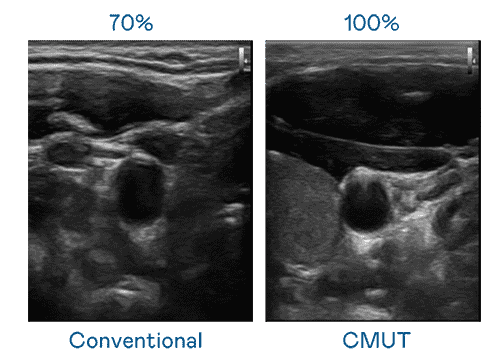

CMUT 技术是一种用电容式微机电元件来产生超音波讯号的技术。。。。与传统 PZT 压电式技术相比,,,,CMUT 频宽增加 30%,,更宽频的超音波讯号让影像解析度大幅提升,,,,是实现高影像品质医疗超音波扫描、、、、促进精准医疗发展的关键技术。。。

大频宽带来超清晰影像

超音波影像的解析度高低,,首先取决于探头能发出的讯号频宽。。。EBpay CMUT 可提供高清晰的超音波讯号,,提供高频宽、、、、高灵敏度、、影像纹理细节更高的超音波影像,,,,协助医护人员缩短影像判读时间及利用精准的医疗影像进行诊断。。。。